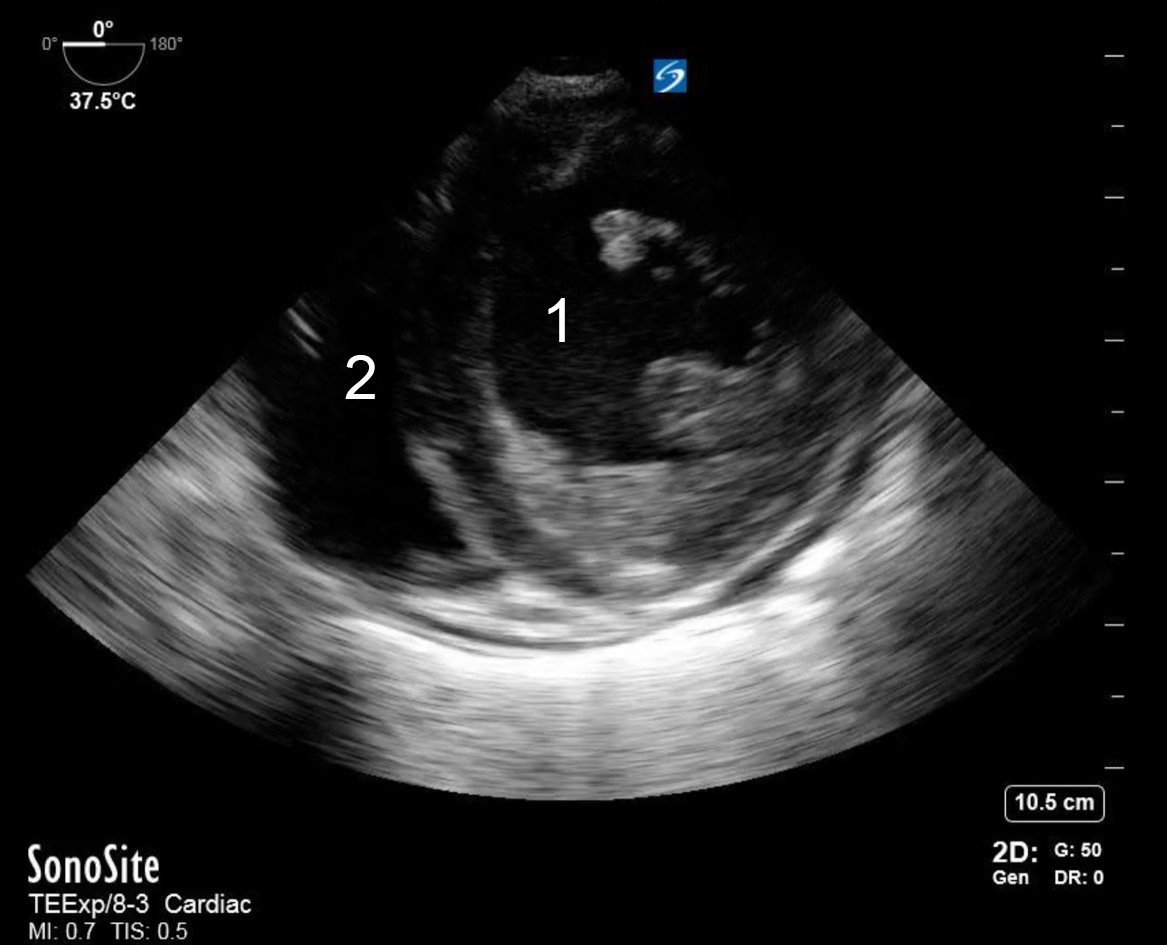

TEE Resus Transgastric Short Axis Image

Left Ventricle

Right Ventricle